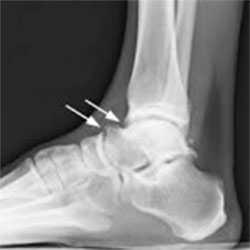

Визуализация переднего большеберцово-таранного импинджмента.Рекомендовано использовать прямую, боковую и косую проекцию при выполнении рентгенографии. На рентгенограммах определяются костные шипы в области дистального отдела большеберцовой кости или по тыльной поверхности таранной кости. Косые проекции позволяют определить остеофиты по передне-медиальной поверхности. КТ и МРТ позволяют более детально оценить степень разрастания остеофитов и их локализацию.

Рентгенография голеностопного сустава в боковой проекции, показывающая костные разрастания в области нижнего отдела большеберцовой кости и шейки таранной кости